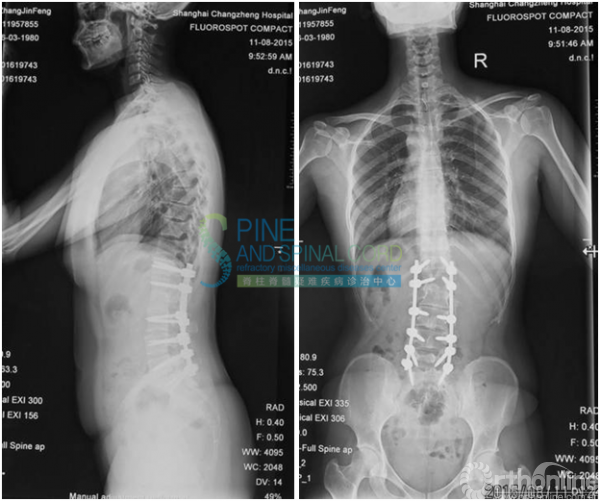

病例四 脊髓栓系综合征伴脊髓纵裂

患者女,34岁,因左下肢疼痛2年,加重1年入院;

2年前无明显诱因出现双下肢疼痛,近1年疼痛加重,不能久坐。无排便排尿困难,无鞍区感觉障碍;

体检:四肢肌力5级,双下肢腱反射亢进,病理征未引出。

术后1年复查平片